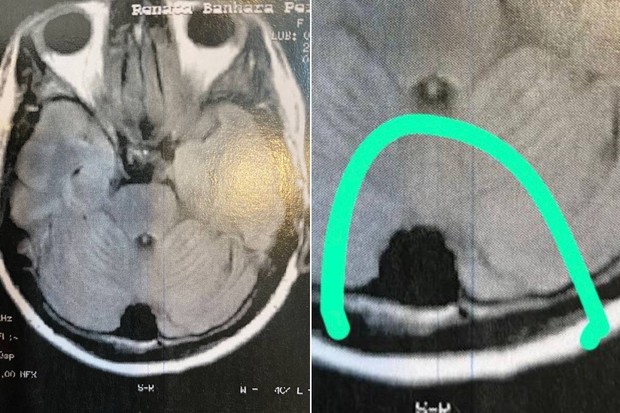

Renata Banhara diz que tumor aumentou e revela que é impossível operar

O tumor no cérebro da modelo Renata Banhara cresceu a tal ponto que não é possível ser operado. Ela revelou que o tumor cresceu de 2mm para 2 cm em três anos

“O tumor está em uma região atrás da minha cabeça, bem no centro da massa cefálica, não tem como extrair, a gente não sabe das consequências. A confiança é que vai estagnar”, explica.

Segundo a modelo, de 46 anos, o tumor que surgiu após fazer um tratamento de canal dentário em 2017, cresceu de dois milímetros para dois centímetros, nos últimos três anos. A doença disseminou uma bactéria incubada em seu organismo, que se alastrou pelo tecido ósseo, causando uma sinusite e depois atingindo as meninges. O acúmulo de bactérias se alastrou ainda mais, comprometendo os nervos e tecidos internos da cabeça, gerando fortes dores no seio da face. A modelo teve paralisia facial e, como consequência, uma forte infecção cerebral que a deixou entre a vida e a morte na UTI.

Tumor no cérebro cresceu de 2 mm para 2 cm | FOTO: Arquivo Pessoal/Renata Banhara via Quem

As fortes dores de cabeça que tinha no início da doença, pelo menos, cessaram. Porém, apesar de ser na região atrás da cabeça, o tumor causa estufamente ósseo na testa.